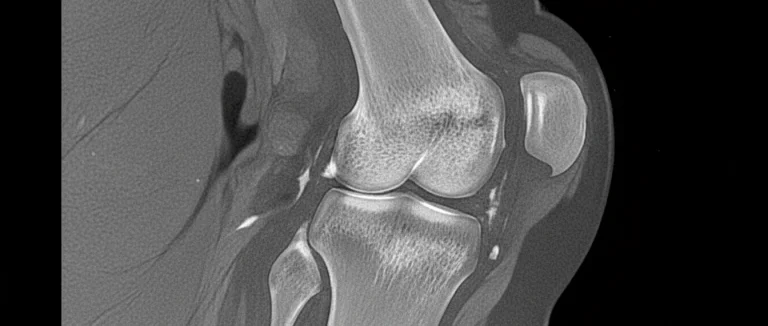

Терапия основана на способности мезенхимальных стволовых клеток дифференцироваться в хрящевые клетки (хондроциты) и стимулировать регенерацию повреждённого хряща. Клетки обычно берутся из жировой ткани пациента (аутологичный материал) или из костного мозга, после чего их культивируют в лаборатории и вводят непосредственно в сустав.

Исследования показывают, что после инъекции происходит частичное восстановление эластичного хряща и улучшение его механических свойств, что особенно важно при артрозе коленного сустава.

Терапия подходит как для ранних стадий, когда хрящ ещё частично сохраняется, так и для более продвинутых форм, когда требуется более интенсивное восстановление.